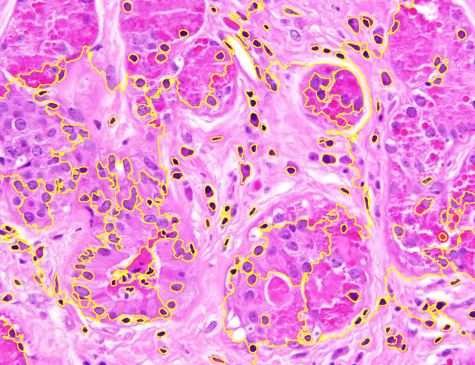

Dataset 1 comprises a synthetic video and two hematoxylin and eosin (H&E)-stained images collected from public online sources [71, 72]. H&E staining is standard in histopathology, with nuclei appearing blue–purple and cytoplasm pink. The images are provided in RGB format with varying image sizes and are used solely for qualitative illustration and timing comparisons, as no ground-truth annotations are available. The synthetic video consists of 74 MATLAB-generated frames. The first frame shows a 3D mitochondrial mesh generated via the isosurface function and rendered with Phong illumination, with the light source positioned above and to the right of the camera. Subsequent frames are obtained by rotating this initial view. This dataset was constructed to study segmentation under pronounced frame-to-frame illumination changes.

Representative samples from the three datasets are shown in Fig. 1. In (a), the first frame of the synthetic video in Dataset 1 illustrates the strong illumination gradients produced by distance-dependent shading together with orientation-dependent interactions between vertex normals and the light direction. The H&E images in (b) and (c), also from Dataset 1, depict a mast cell infiltrate from a patient with non-alcoholic steatohepatitis and cirrhosis and, respectively, a sample from a patient with sclerosing polycystic adenosis of the parotid gland; the former consists primarily of purple nuclei, white cytoplasm, and pink extracellular tissue. Subfigures (d) and (e) show two examples from Dataset 2 accompanied by their ground-truth nuclei annotations, while (f) and (g) present a representative image from Dataset 3 together with its corresponding cell mask.

Figure 1: Samples from Datasets 1–3. (a) First frame of the 74-frame video in Dataset 1 (1770 × 880) with a superimposed red mesh. (b,c) H&E-stained tissue images from Dataset 1 (1000 × 750; 950 × 730). (d,e) Cell images from Dataset 2 (600 × 600) with nuclei annotations. (f,g) Image from Dataset 3 (512 × 512) with annotation.

Figure 9 shows the segmentation results for the first hematoxylin and eosin (H&E)–stained image from Dataset 1 (see Fig. LABEL:fig_sub:he1_image). Initial level sets and superpixels are shown in Figs. LABEL:fig_sub:he1_in1_zz-LABEL:fig_sub:he1_in_SP: AR and ZZ used two distinct level sets for nuclei (S1) and cytoplasm (S2) (Figs. LABEL:fig_sub:he1_in1_zz-LABEL:fig_sub:he1_in2_zz), while SP and SMST (Fig. LABEL:fig_sub:he1_in_SP) used the same set of 4000 Power-SLIC superpixels in the same color space (red channel for S1, remaining channels for S2). SAM does not allow separate-channel segmentation; its combined S1/S2 result is shown in Fig. LABEL:fig_sub:he1_out_SAM. Figures LABEL:fig_sub:he1_out1_AR-LABEL:fig_sub:he1_out1_SP display S1 results for AR, ZZ, SMST, and SP, and Figs. LABEL:fig_sub:he1_out2_AR-LABEL:fig_sub:he1_out2_SP show the corresponding S2 results.

AR seemed highly sensitive to initialization, segmenting mainly regions near seed points and requiring seeds in nearly all connected foreground components for satisfactory performance. ZZ segmented a wider range of objects from fewer seeds but incorrectly included nuclei in cytoplasm segmentation, failing to capture white regions and introducing spurious tissue. SAM automatically detected many nuclei and some cytoplasm but merged all structures into a single segmentation, limiting its practical utility here. SMST was the fastest but failed to recover large homogeneous regions, such as the background, and frequently fragmented them due to its variance-based metric. In contrast, SP yielded the most accurate results on both S1 and S2, with clear background separation and precise boundary delineation.

Figure 9: Unsupervised segmentation of the image in Fig. LABEL:fig_sub:he1_image for two structures: purple cells (S1) and white cytoplasm (S2). Initializations via level sets (LS) for AR and ZZ are shown in (a, b); 4000 superpixels for SMST and SP in (c) (red channel for S1, remaining channels for S2). SAM does not allow separate-channel segmentation; its overall output is in (d). Results for S1 are in (e–h) and for S2 in (i–l). Computation times (S1/S2, in seconds): AR 829.51/570.32, ZZ 4304.50/4470.56, SMST 0.38/0.38, SP 5.98/4.26; superpixels in (c) computed in 0.17s, SAM in (d) in 7.42s.